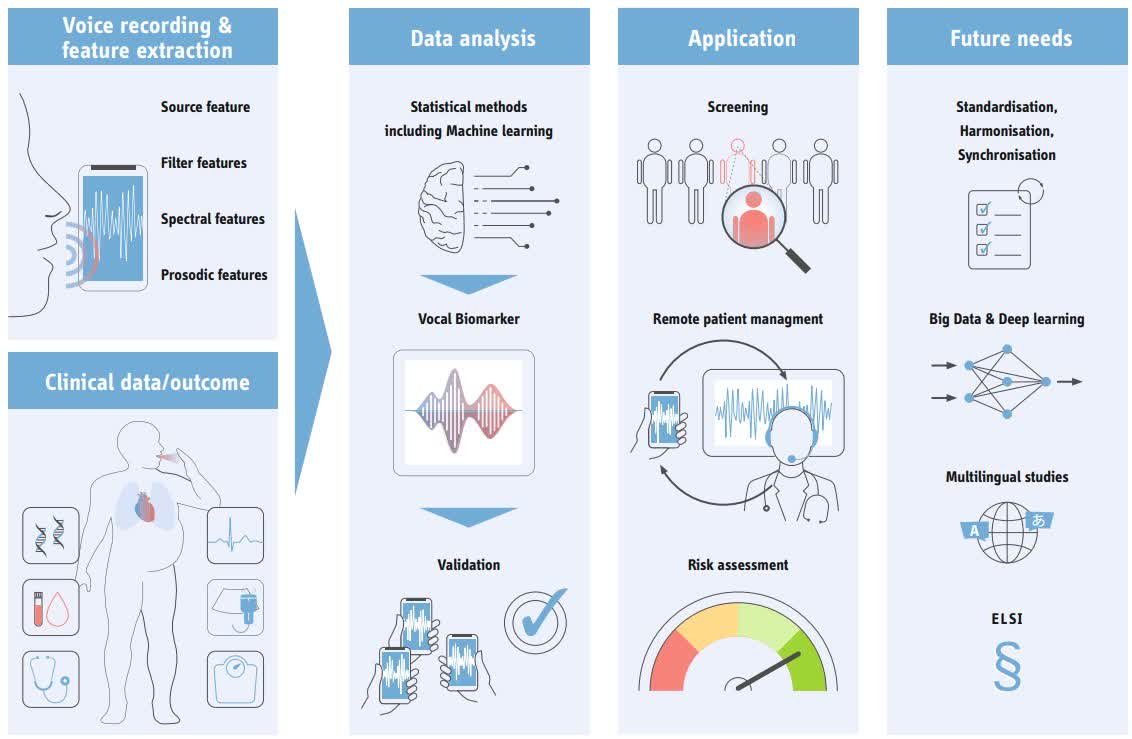

#Vocal biomarkers in #heart failure – a promising tool for telemonitoring, explored in our systematic review #AI #VoiceAnalysis #AHAJournals Maximilian Bauser Deutsches Zentrum für Herzinsuffizienz ahajrnls.org/4cWqdtq